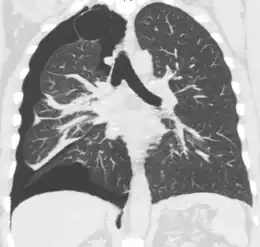

Computed tomography

A CT scan is not necessary for the diagnosis of pneumothorax, but it can be useful in particular situations. In some lung diseases, especially emphysema, it is possible for abnormal lung areas such as bullae (large air-filled sacs) to have the same appearance as a pneumothorax on chest X-ray, and it may not be safe to apply any treatment before the distinction is made and before the exact location and size of the pneumothorax is determined.[14] In trauma, where it may not be possible to perform an upright film, chest radiography may miss up to a third of pneumothoraces, while CT remains very sensitive.[17]

A further use of CT is in the identification of underlying lung lesions. In presumed primary pneumothorax, it may help to identify blebs or cystic lesions (in anticipation of treatment, see below), and in secondary pneumothorax it can help to identify most of the causes listed above.[14][18]